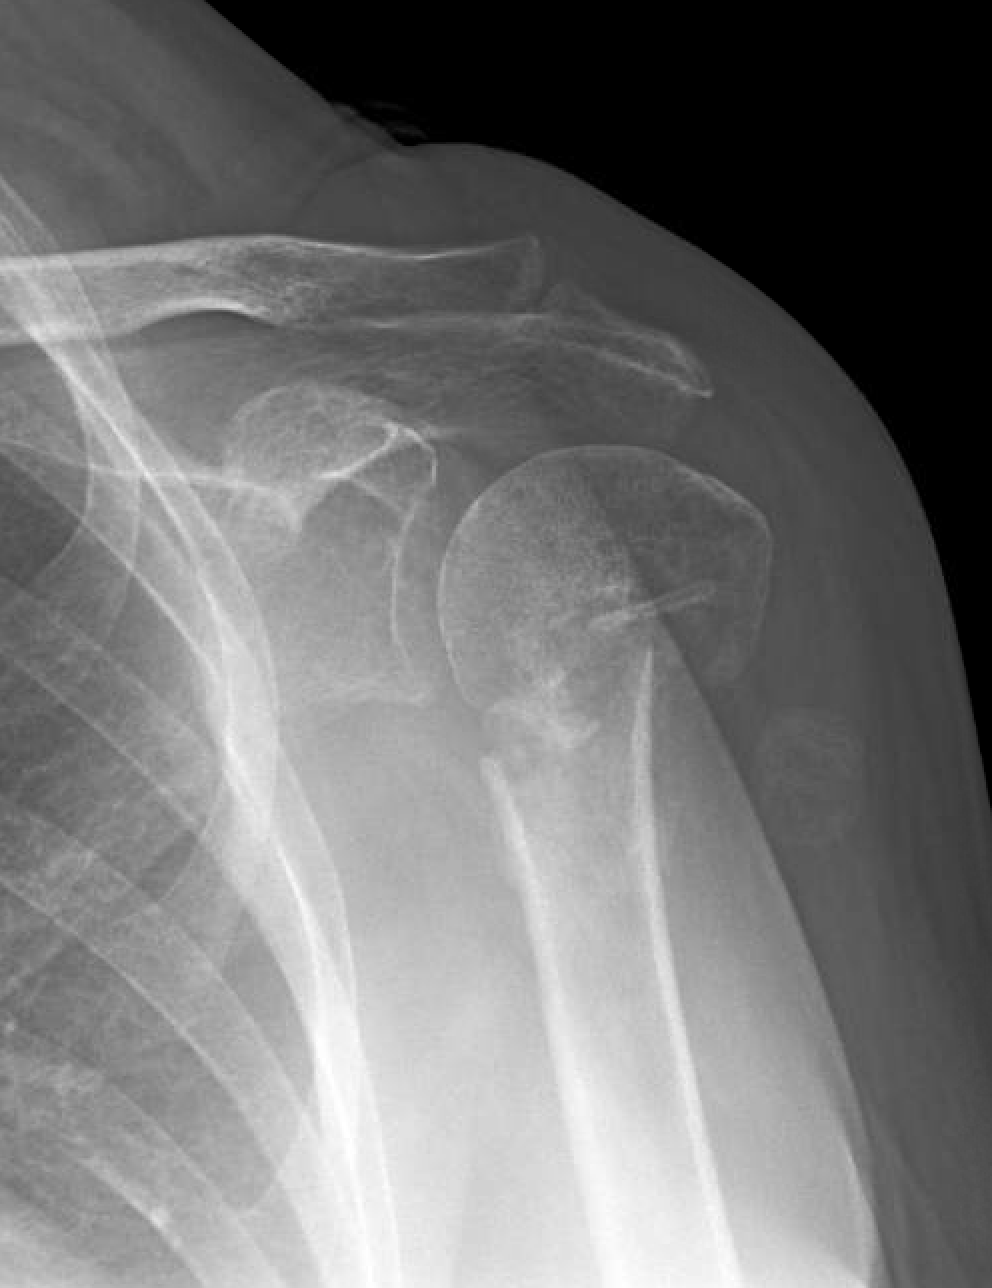

Radiographs showing a right elbow with a typeIIIB fracture, a coronoid Elbow Fracture Non Operative Protocol • protocol must be altered based on fixation strength at. Rom by end of 2nd week should be at least 15 to 115. • continue to control pain and edema as needed •. This protocol is recommended for mason’s type i fracture or type ii or iii with orif. Rehabilitation protocol nonoperative radial head fracture. Passive and active elbow rom. Elbow Fracture Non Operative Protocol.